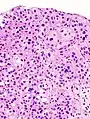

The 1973 WHO grading system for transitional cell carcinomas (papilloma, G1, G2 or G3) is most commonly used despite being superseded by the 2004 WHO[14] grading for papillary types (papillary neoplasm of low malignant potential [PNLMP], low grade, and high grade papillary carcinoma). High-grade carcinoma typically displays more pleomorphism, multiple mitoses, euchromatin and relatively prominent nucleoli, and uneven distribution of nuclei.

Transitional cell carcinoma, being low-grade to the left, and high-grade to the right. H&E stain

Histopathology of urothelial carcinoma of the urinary bladder.